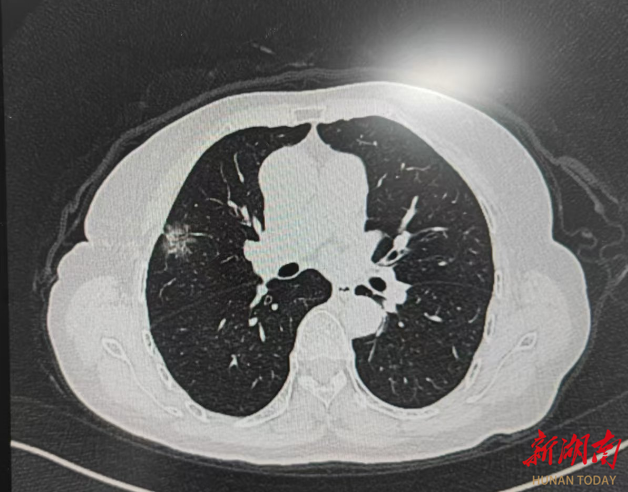

患者为62岁女性,CT显示右上肺1.9 cm磨玻璃结节,综合各项检查检验结果判断,考虑原发肺癌可能性大,需手术切除。患者于2025年3月12日行LungCare电磁导航支气管镜定位联合胸腔镜行肺结节精准切除术。

针对部分肺小结节,如果术前不做准确定位,术中寻找会有一定难度。以往采用的CT引导肺穿刺定位,无论是穿刺定位针或者穿刺注射染色剂,患者术前都要接受数次CT放射性暴露;与此同时,穿刺定位过程中血气胸、针道种植转移等并发症都是需要考虑的。目前,电磁导航支气管镜定位技术是最为无创最安全最快捷的定位方式,运用电磁导航定位,可以实现一体化手术室对肺结节的精准诊治和快速康复。

确认术前路径规划后,张昌红主治医师运用LungCare电磁导航,精准定位肺结节,用时仅六分钟。

在电磁导航的引导下,实现无创、实时、快速、精准的定位标记。